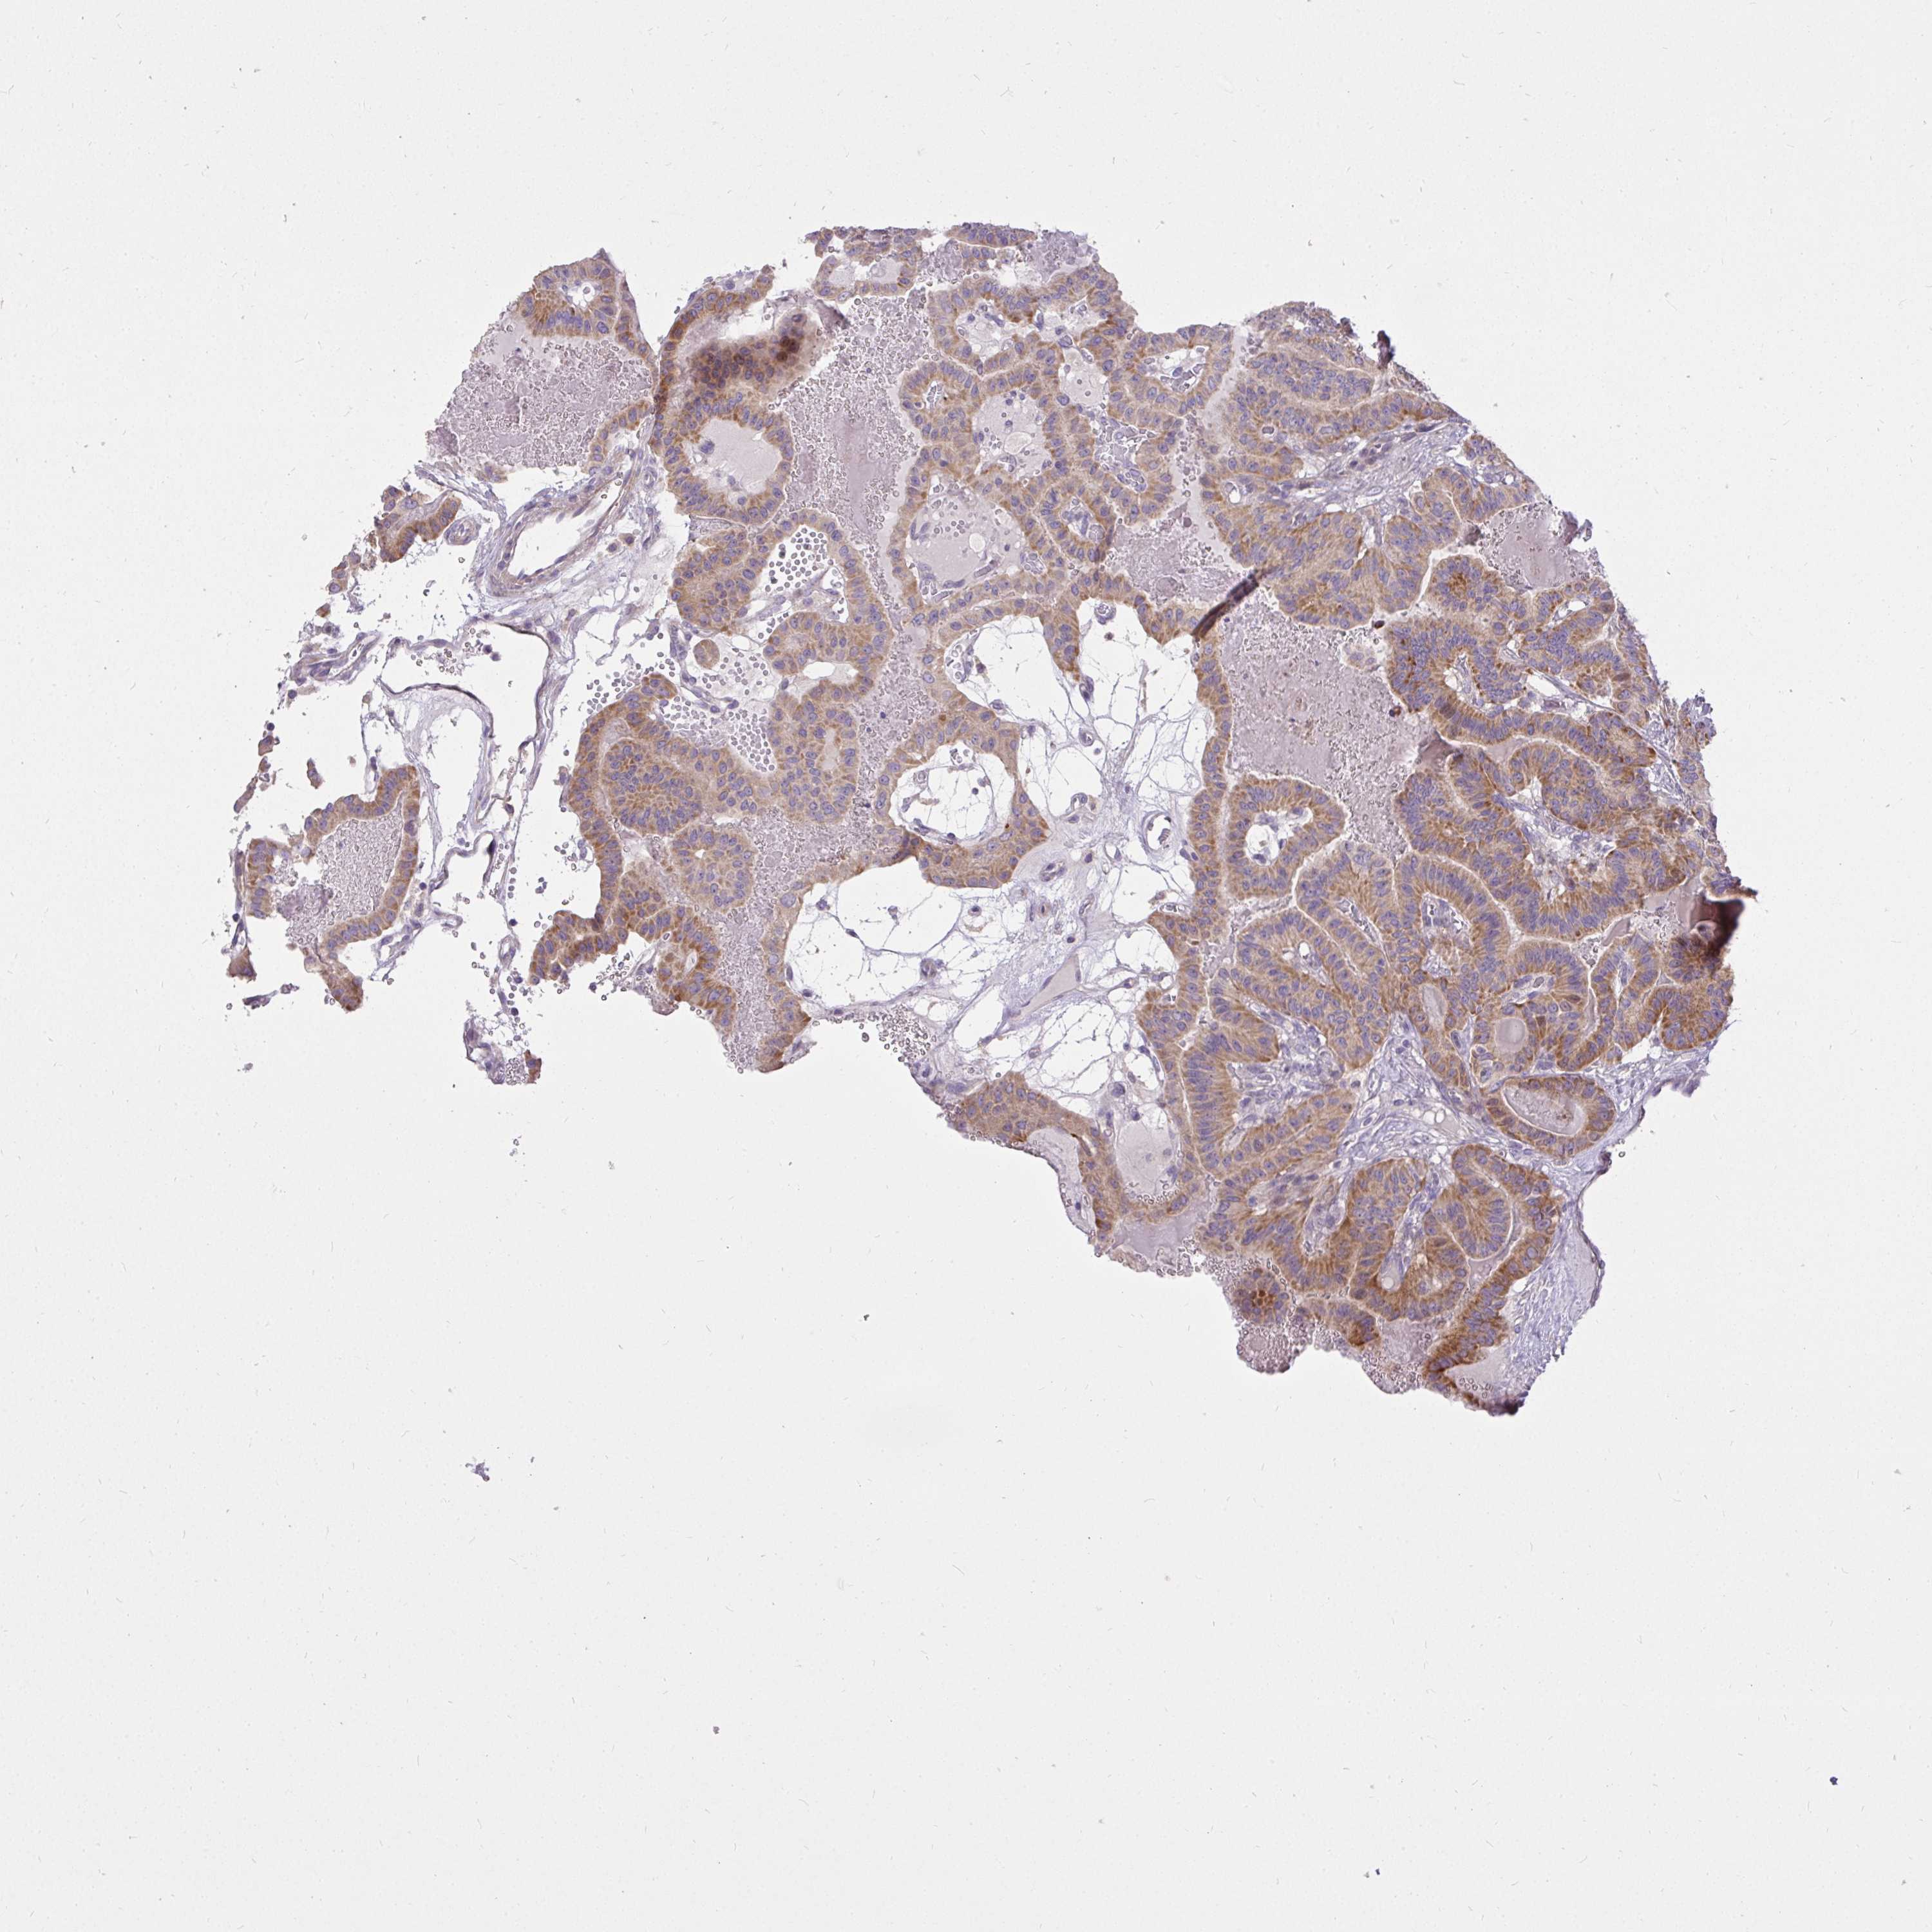

THYROID CANCER - Protein expressioni

A mouse-over function shows sample information and annotation data. Click on an image to view it in a full screen mode. Samples can be filtered based on level of antibody staining by selecting one or several of the following categories: high, medium, low and not detected. The assay and annotation is described here.

Note that samples used for immunohistochemistry by the Human Protein Atlas do not correspond to samples in the TCGA dataset.

Antibody stainingi

Antibody staining in the annotated cell types in the current human tissue is reported as not detected, low, medium, or high, based on conventional immunohistochemistry profiling in selected tissues. This score is based on the combination of the staining intensity and fraction of stained cells.

Each image is clickable and will lead to virtual microscopy that enables deeper exploration of all samples and also displays staining intensity scores, fraction scores and subcellular localization as well as patient and tissue information for each sample.

Antibody HPA060302

Staining

High

Medium

Low

Not detected

Intensity

Strong

Moderate

Weak

Negative

Quantity

>75%

75%-25%

<25%

None

Location

Nuclear

Cytoplasmic/membranous

Cytoplasmic/membranous,nuclear

Papillary adenocarcinoma, NOS

Follicular adenoma carcinoma, NOS